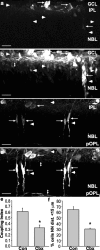

During development of the retina, programmed cell death helps to establish the final size and distribution of various cell classes in distinct layers of the tissue. Here we show that dying cells in the developing ganglion and inner nuclear layers are clustered spatially and that gap junction inhibitors decrease the clustering of dying cells. To confirm the role of gap junctions in cell death, we induced targeted cell death via intracellular cytochrome c (Cc) and examined the induced cells and their neighbors for apoptotic morphology or caspase-3 cleavage. These studies indicate that bystander killing extends to coupled cells. Quantitative studies of bystander killing were performed by scrape-loading retinas with Cc in the presence of rhodamine dextran (RD; to identify Cc-loaded cells) and by counting pyknotic cells in cryosections. Although only 1.5% of control scrape-loaded cells (RD alone) showed apoptotic morphology, 97% of Cc scrape-loaded cells were pyknotic. Moreover, bystander killing extended to neighboring cells, not labeled with RD, and was reduced significantly by the gap junction inhibitors octanol and carbenoxolone. We hypothesize that dying cells in the retina generate a gap junction-permeant apoptotic signal that mediates bystander killing. This novel finding of naturally occurring bystander cell death may have important implications in the histogenesis and pathology of the nervous system.